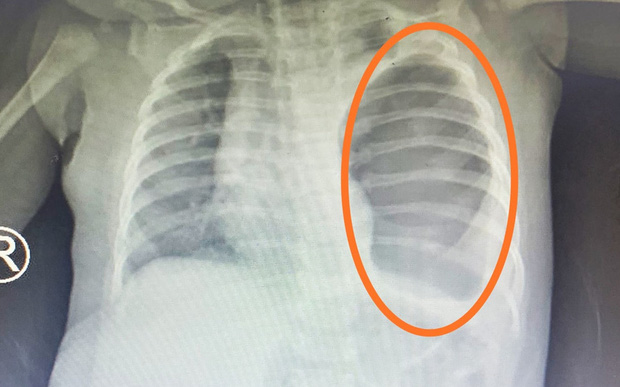

Tại bệnh viện, kết quả xét nghiệm, siêu âm ổ bụng và chụp X-quang của bé cho thấy: Hình ảnh dạ dày, quai ruột chiếm toàn bộ phổi trái, chèn ép đẩy lệch tim sang bên phải. Các bác sĩ chẩn đoán: bé bị thoát vị hoành, nếu không được mổ kịp thời để sắp xếp lại vị trí các tạng trong ổ bụng và lồng ngực, bé có thể tử vong bất kỳ lúc nào.

Sau khi hội chẩn, điều trị hồi sức tích cực, bé được phẫu thuật mổ nội soi cấp cứu. Trong quá trình phẫu thuật, BSCKII. Tạ Huy Cần, Trưởng Khoa Ngoại tổng hợp và các bác sĩ phát hiện toàn bộ ruột non, ruột già, lá lách thoát vị nằm hoàn toàn trên khoang màng phổi.

Tùy thuộc vào lỗ thoát vị to hay nhỏ mà các phủ tạng có thể chui lên lồng ngực như dạ dày, ruột non, lách. Đây là ca bệnh khó, hiếm gặp ở trẻ sơ sinh khi hầu hết các bộ phận nội tạng ở vùng bụng đã chui lên lồng ngực. Nếu để sinh ra mới phát hiện thì tỷ lệ tử vong là rất cao.